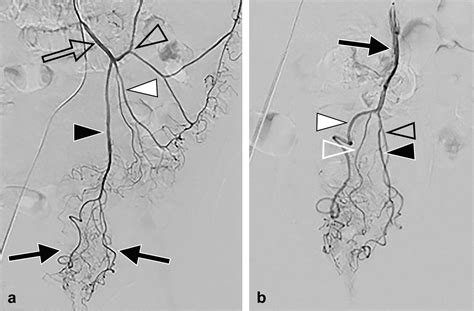

Because it is a minimally invasive technique, it does not require general anesthesia or incisions in the sensitive anal region. Instead, a tiny catheter is guided through a blood vessel in the wrist or groin to the specific arteries supplying the hemorrhoids. Small particles are then injected to block these vessels, successfully reducing the pressure and engorgement of the hemorrhoidal tissues.

2. Guidance: Using real-time X-ray imaging (fluoroscopy), the radiologist navigates a microcatheter through the vascular system.

3. Embolization: Once the specific hemorrhoidal arteries are identified, specialized embolic agents are injected to reduce the blood supply.